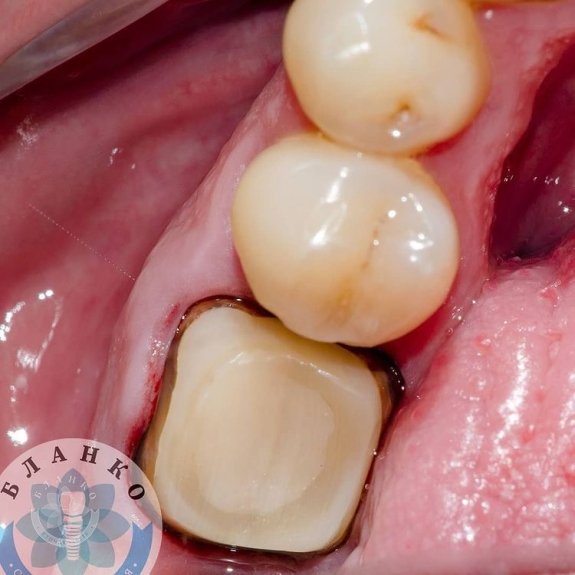

- тверді тканини зуба відновлені за допомогою спеціального матеріалу

- знято відбитки та виготовлено високоміцну, гіпоалергенну та високоестетичну коронку з діоксиду цирконію.